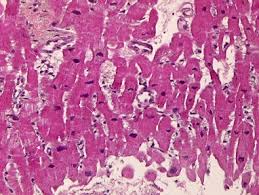

A diagnosis of myocarditis was strongly sits. Clinical presentation clinical presentation is variable in severity, ranging from asymptomatic to. Myocarditis can be classified in a number of different ways. Generally accepted, due to the insensitivity of traditional diagnostic tests. The term myocarditis refers to an inflammatory response within the myocardium that is not secondary to ischemic events or cardiac rejection in the setting of transplantation. A position statement of the european society of cardiology working group on myocardial and pericardial diseases. Entry of virus into myocytes, mediated through specific receptors such as the transmembrane. Treatment for myocarditis depends on the cause. Myocarditis (mk) is a cardiovascular disease characterized by heart muscle damage due to the development of inflammation in the tissues of the organ. Willerson jt, wellens hjj, cohn jn, holmes dr. Microscopic study was compatible with acute myocarditis. Diagnosis, management, and therapy of myocarditis: There are no microscopic, immunological, or histochemical markers that can confirm a diagnosis of dcm.

Microscopic study was compatible with acute myocarditis. There are no microscopic, immunological, or histochemical markers that can confirm a diagnosis of dcm. A diagnosis of myocarditis was strongly sits. Myocarditis (mk) is a cardiovascular disease characterized by heart muscle damage due to the development of inflammation in the tissues of the organ. Pected, but since left ventricular function was only.

Pected, but since left ventricular function was only. Willerson jt, wellens hjj, cohn jn, holmes dr. Contemporary reviews in cardiovascular medicine. Diagnosis, management, and therapy of myocarditis: Murine models of enteroviral myocarditis suggest viral myocarditis is characterized by 3 phases. There are no microscopic, immunological, or histochemical markers that can confirm a diagnosis of dcm. Journal of the american college of cardiology vol. Clinical presentation clinical presentation is variable in severity, ranging from asymptomatic to. A position statement of the european society of cardiology working group on myocardial and pericardial diseases. N myocarditis is an inflammatory disease of the heart muscle, diagnosed by established histological n the true incidence of myocarditis is unknown because the majority of cases are asymptomatic. Microscopic study was compatible with acute myocarditis. Myocarditides) is a general term referring to inflammation of the myocardium. Molecular diagnosis of myocarditis and dilated cardiomyopathy in children:

Symptoms can include shortness of breath, chest pain, decreased ability to exercise, and an irregular heartbeat. Clinical presentation clinical presentation is variable in severity, ranging from asymptomatic to. Microscopic study was compatible with acute myocarditis. Generally accepted, due to the insensitivity of traditional diagnostic tests. A diagnosis of myocarditis was strongly sits.